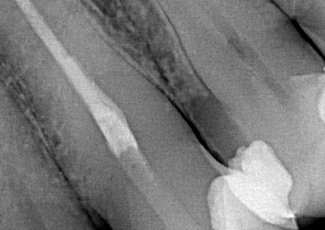

Іригацію здійснили 5% розчином гіпохлориту натрію та 17% розчином ЕДТА. Спредери такої довжини (31 мм) були відсутні, тому не могли провести латеральну конденсацію в апікальній третині каналу; для застосування методики класичної хвилі довжина каналу також критична (down-пакер так далеко не зайде, особливо з урахуванням ще й невеликого доступу). Тому в якості силера було вибрано біокерамічний матеріал SURE-SEAL ROOT (SURE DENT), обтурація виконана згідно з технікою холодного майстер-штифта.

Особливості клінічного випадку вимагали віддати перевагу біокерамічному силеру для обтурації кореневих каналів – SURE-SEAL ROOT (SURE DENT). Його фізико-хімічні властивості дозволили отримати максимально прогнозований, швидкий та ефективний результат лікування.